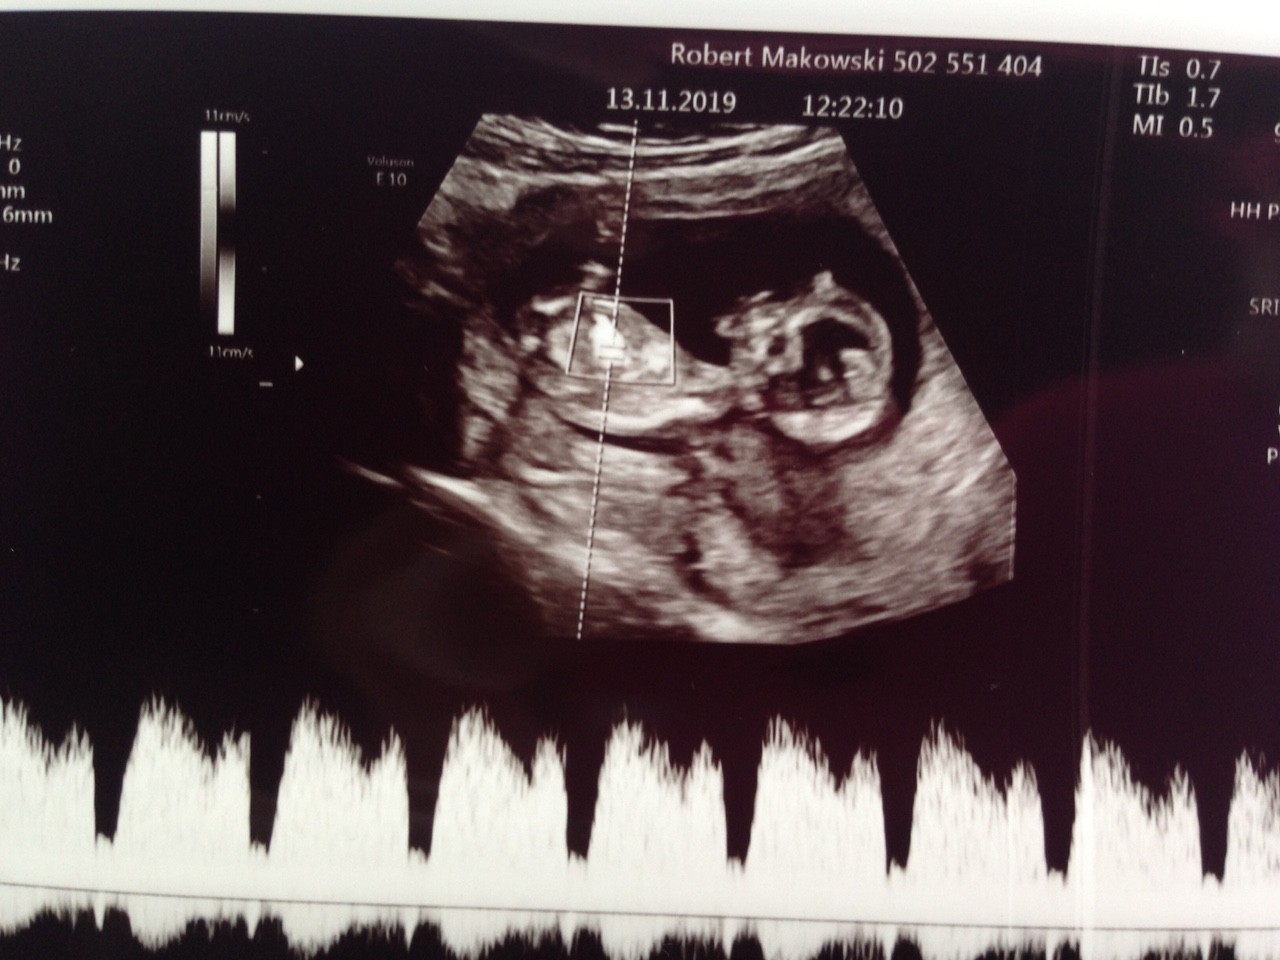

Jutro mam usg genetyczne (12+3).

Dzisiaj odebrałam wynik biochemii krwii.

Rozumiem, ze nie ma sensu tero analizować dopóki nie odbędę wizyty?

IMG_1233.JPG